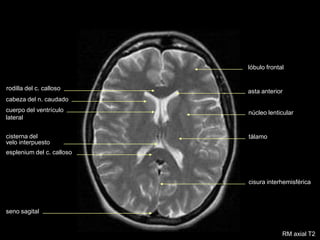

asta anterior

cuerpo del ventrículo

lateral

rodilla del c. calloso

cabeza del n. caudado

cisterna del

velo interpuesto

esplenium del c. calloso

núcleo lenticular

tálamo

cisura interhemisférica

seno sagital

lóbulo frontal

RM axial Densidad Protónica